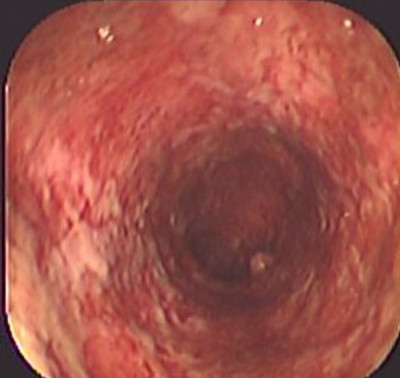

Colitis ulcerosa crónica inespecífica

Envíado por Dr. Carlos Ernesto Arévalo